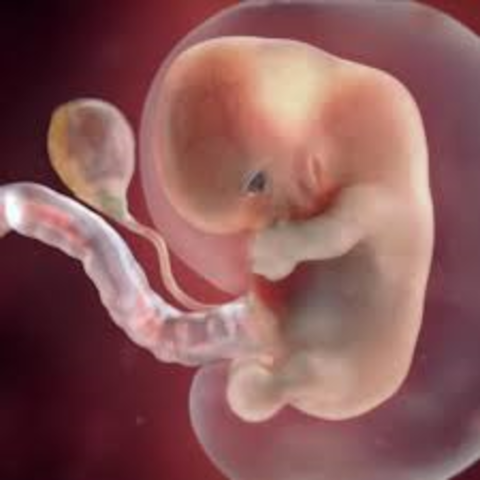

Week 5

The embryo now starts the process of shaping into a human. The placenta is developing and amniotic fluid begins to build up whcih will surround the fetus. The embryo is about 2-5mm.